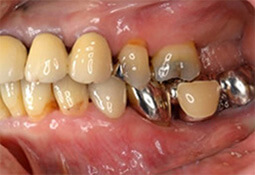

奥歯治療の特殊性について

奥歯特有の複雑な解剖学的形態

複雑に枝分かれした歯根形態に注目

インプラント治療の対象部位を見てみると前歯に比べ奥歯の頻度が多いのが現状です。では何故奥歯を失う患者様が多いのでしょうか?その大きな原因の一つとして奥歯特有の複雑な解剖学的形態が挙げられます。

図に示した様に、前歯は歯根が1本であるのに対し奥歯の歯根は殆どが複数本でその形態も複雑です。正確なブラッシングも難しく、また歯周病(細菌感染)が一旦歯の周囲に拡大すると確実な細菌の除去が難しくなります。

抜歯以外の選択肢

感染の入口である分岐部の狭さにも注目

その難しさ故に早期に抜歯→インプラント治療も一つの治療方法ではありますが、その前に即抜歯ではなく奥歯の一部分を抜去・分割等することにより、歯周病治療が可能となり、ひいてはその歯の保存も可能な場合があります。その1部をご覧ください。

歯の1部分を抜去することにより感染拡大を未然に防ぐことが可能です。

歯間ブラシ等磨き易い形態に治療・修正することも可能です。

以上示した治療例は、全て術後約10年間機能しております。